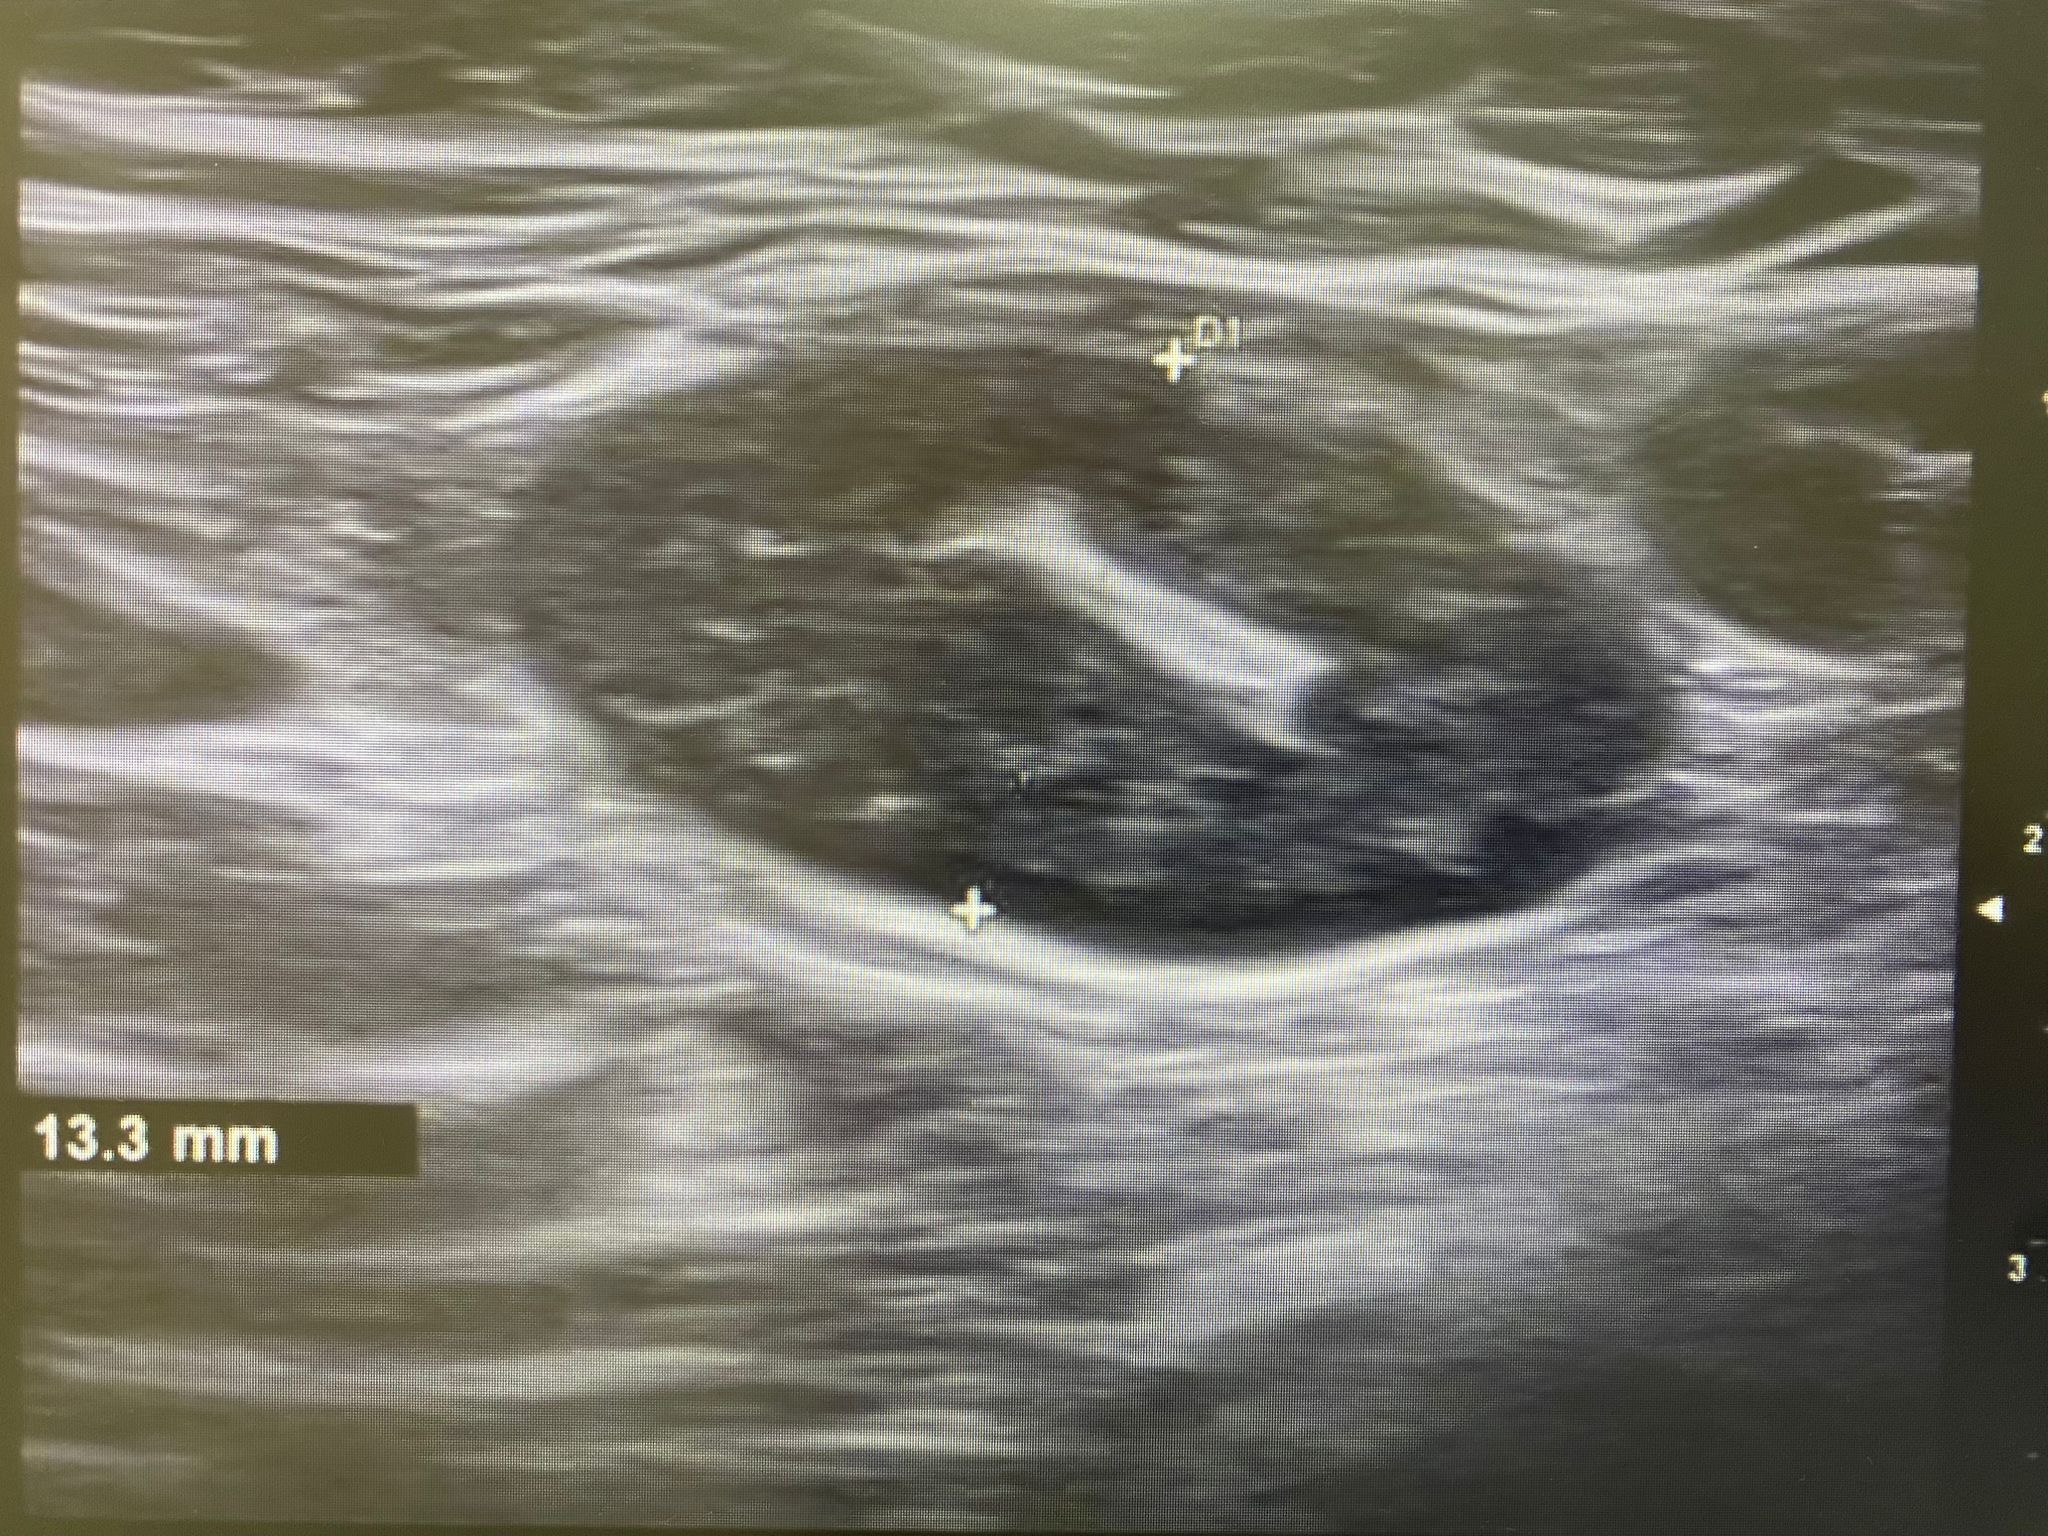

Ecografía: Valoración de adenopatías para acercamiento diagnóstico (típicas/atípicas).

Hallazgos ecográficos

Adenopatías patológicas, algunas redondeadas, con eje anteroposterior > 1 cm, parénquima homogéneo, cortical engrosada aunque con hilio respetado.

Ecografía mamas: quistes y nódulos hipoecogénicos bilaterales.

Ecografía axilar: múltiples adenopatías con eje corto > 2 cm y cortical engrosada.